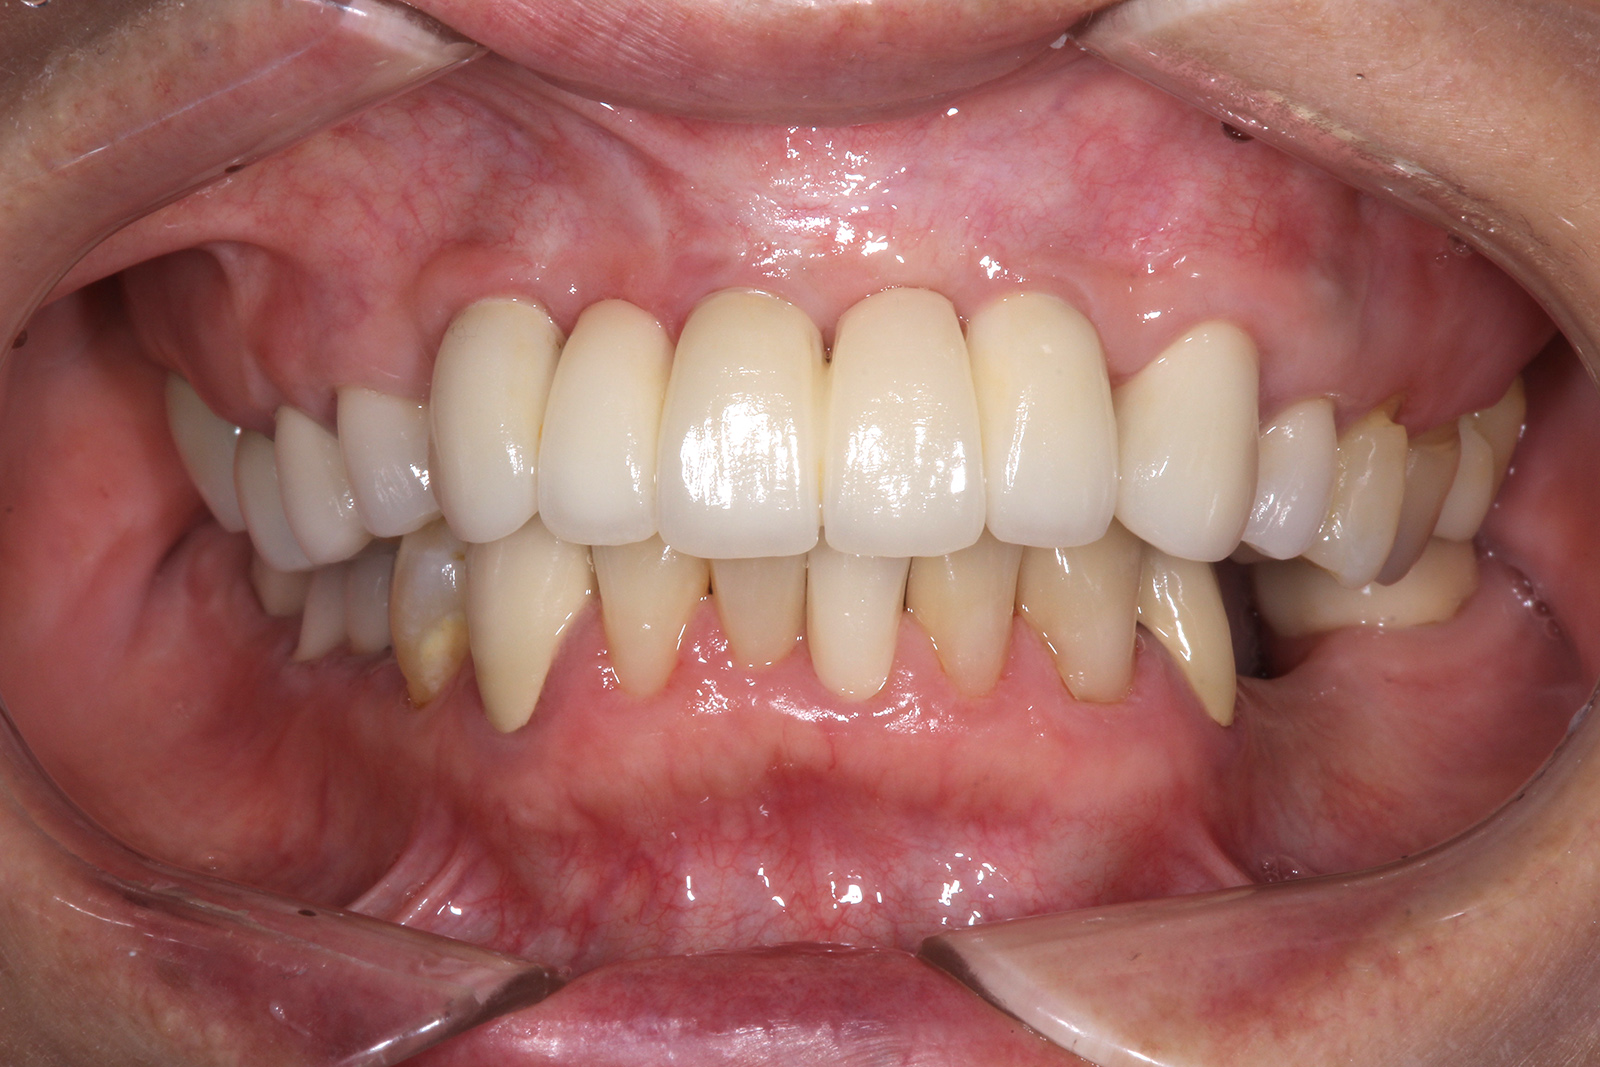

• 治療前

• 治療後

お口全体の治療。インプラント治療の他、ブロック骨移植や結合組織移植、全顎矯正などを行った。治療期間は2年6ヶ月ほど。費用はおよそ500万円。定期的なメンテナンスを行わないと、インプラント周囲炎のリスクがある。